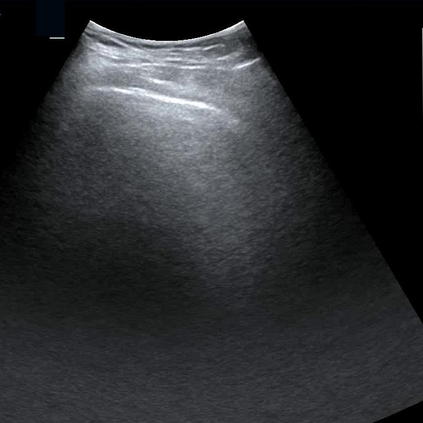

Most deep neural networks (DNNs) based ultrasound (US) medical image analysis models use pretrained backbones (e.g., ImageNet) for better model generalization. However, the domain gap between natural and medical images causes an inevitable performance bottleneck. To alleviate this problem, an US dataset named US-4 is constructed for direct pretraining on the same domain. It contains over 23,000 images from four US video sub-datasets. To learn robust features from US-4, we propose an US semi-supervised contrastive learning method, named USCL, for pretraining. In order to avoid high similarities between negative pairs as well as mine abundant visual features from limited US videos, USCL adopts a sample pair generation method to enrich the feature involved in a single step of contrastive optimization. Extensive experiments on several downstream tasks show the superiority of USCL pretraining against ImageNet pretraining and other state-of-the-art (SOTA) pretraining approaches. In particular, USCL pretrained backbone achieves fine-tuning accuracy of over 94% on POCUS dataset, which is 10% higher than 84% of the ImageNet pretrained model. The source codes of this work are available at https://github.com/983632847/USCL.

翻译:大部分深心神经网络(DNNS)基于超声波(美国)的超声波医学图像分析模型使用预先训练的脊椎(如图像网络)来进行更好的模型化分析。然而,自然图像和医疗图像之间的领域差距造成了不可避免的性能瓶颈。为了缓解这一问题,为在同一领域直接训练建造了一个名为US-4的美国数据集。该数据集包含来自四个美国视频子数据集的23 000多张图像。为了从美国-4中学习强健的特征,我们提议了美国半监督的对比学习方法,名为USCL(USCL),用于预培训。为了避免负面对子与有限的美国视频中丰富的地雷视觉特征之间的高度相似性,USCL采用了一种样品配对生成方法来丰富单步对比性优化所涉及的特征。关于一些下游任务的广泛实验显示了USCL对图像网络预培训和其他状态艺术预培训方法的优势。特别是,USCLU预先训练的骨架在POCS数据集上实现了94 %的微调精准性精确度,这在图像网络上比84%高10 %/MUSPASTASTASTRAIN premstrain practresmex pract press press rodustrismex sramduction sramduction sramduction sramduction surgles)。